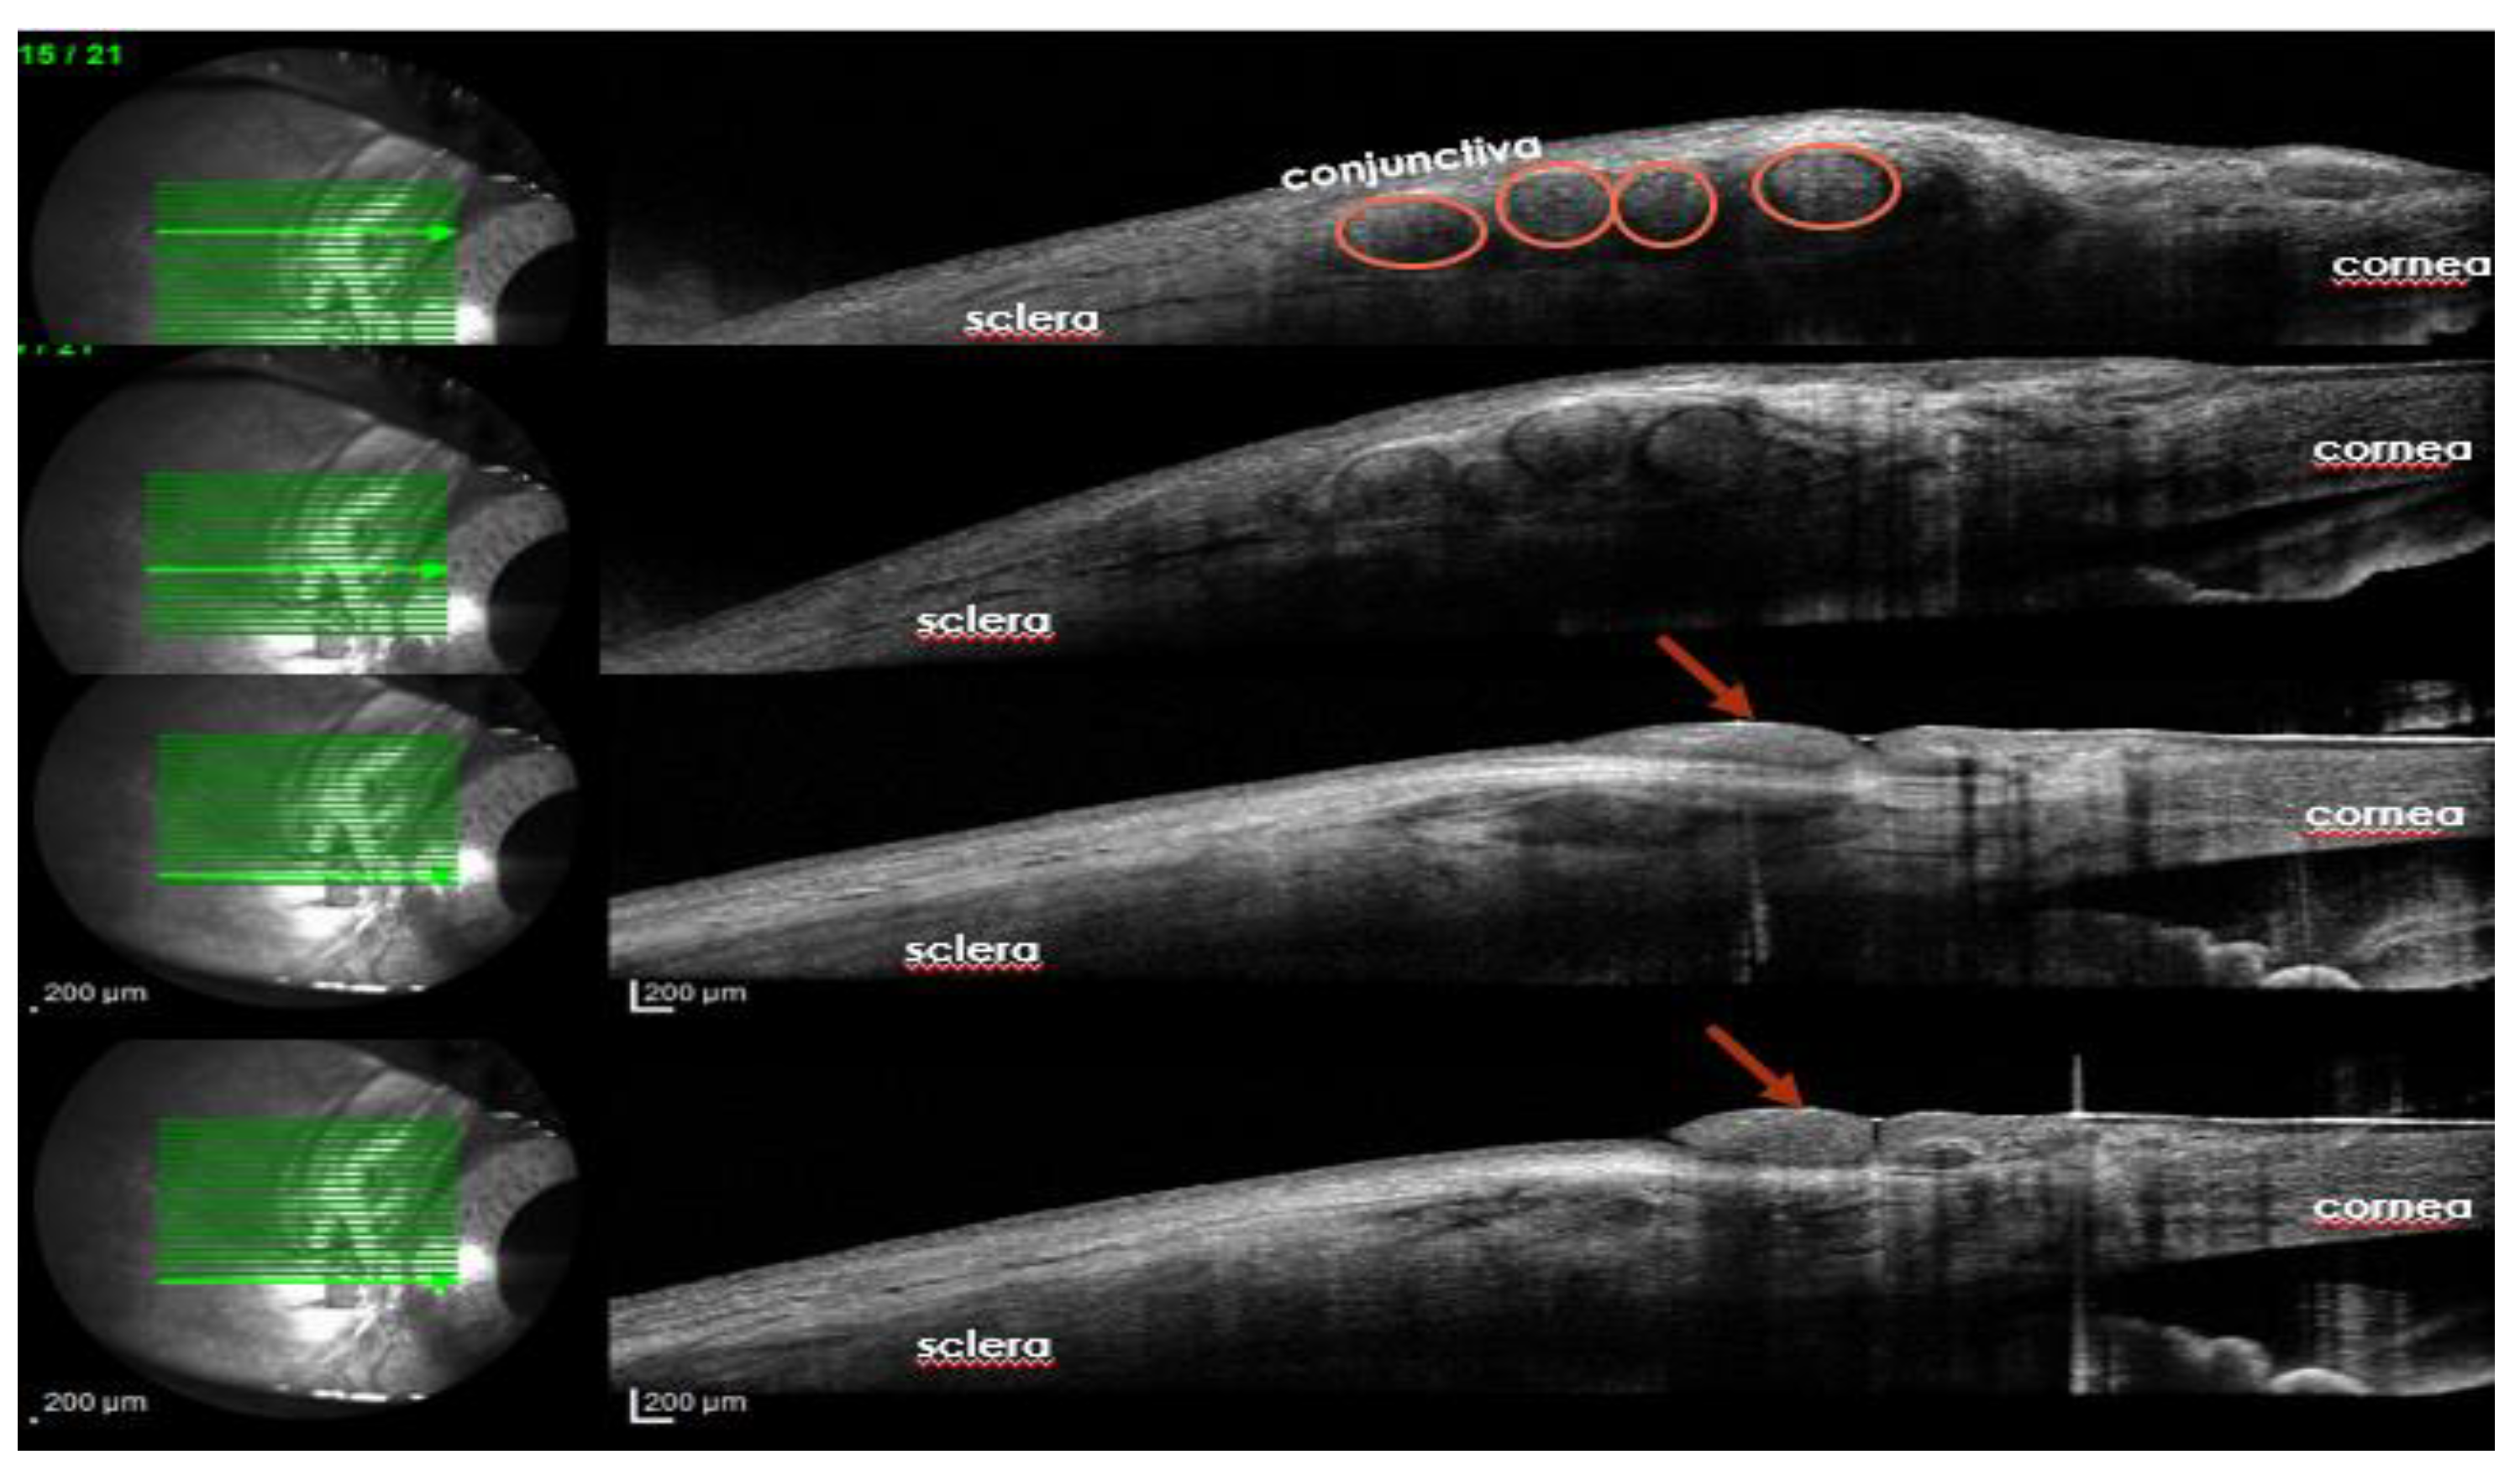

We suggest that the presence of nerve filaments tunneled around the cornea could be observed with ocular coherence tomography (Figure 3). Refinements in anterior segment OCT could improve nerve fiber detection at the level of corneal sub-basal plexus.

Figure 3. Ocular Coherence Tomography, 3 years after corneal neurotization demonstrates the presence of nerve grafts beneath the conjunctiva (cercles) at the level of peripheral cornea (arrows) (personal archive, Samoila Ovidiu).